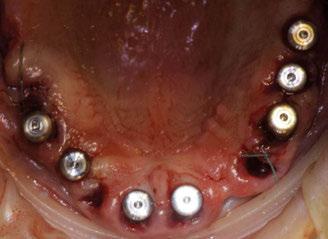

Figura 3. Visión intraoral oclusal mandibular. Figura 4. Visión intraoral frontal. Figura 1. Visión intraoral oclusal maxilar. Figura 2. Visión lateral izquierda intraoral. Figura 7. Escaneado intraoral maxilar con Dexis IS3700. Figura 8. Escaneado intraoral mandibular con Dexis IS3700. Figura 5. Visión extraoral lateral sonrisa.

Figura 23. Férula quirúrgica inferior. Figura 24. Fresado guiado con férula y cucharilla. Figura 20. Extracciones dentales. 21. Conservación Figura 22. Férula quirúrgica superior. Figura 25. Inserción de implante RSX de Bego a través de férula quirúrgica. Figura 27. Conexión de pilar angulado multiplus sobre implante. Figura 26. Implante insertado en lecho a través de férula quirúrgica. Figura 28. Muestra del perfecto paralelismo tras la colocación de pilares angulados multiplus. Figura 29. ScanBody sobre pilares transepiteliales.